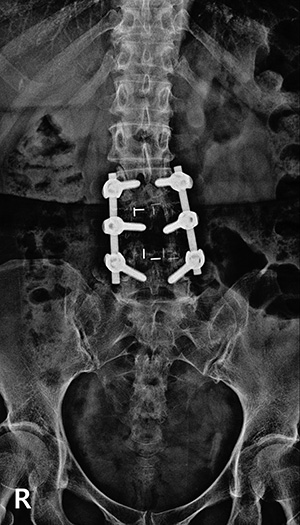

▼ 척추뼈 3개를 묶은 유합술 ▼

유합술 전면 X-ray